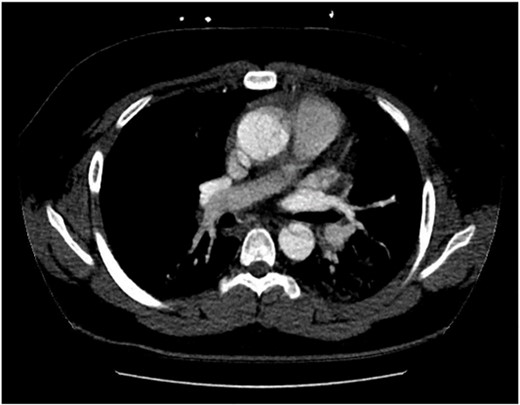

The patient was hemodynamically stable during his admission; however, worsening pain profile led to a serial electrocardiogram showing sinus rhythm with ST segment changes consistent with ischemia. There was an initial troponin rise of 245 ng/L progressing to a peak of 922 ng/L. The remaining blood panel was unremarkable. Chest X-ray showed no widened mediastinum and clear lung fields. A bedside transthoracic echocardiogram demonstrated a dissection flap with severe aortic regurgitation in the ascending aorta. Computed tomography aortogram was consistent with a Stanford Type A aortic dissection extending from the aortic root to the bifurcation of the common iliac arteries (Figs 1 and 2). There was involvement of the right brachiocephalic artery and right common iliac.

Computed tomography aortogram Axial Image of Stanford Type-A Aortic Dissection.